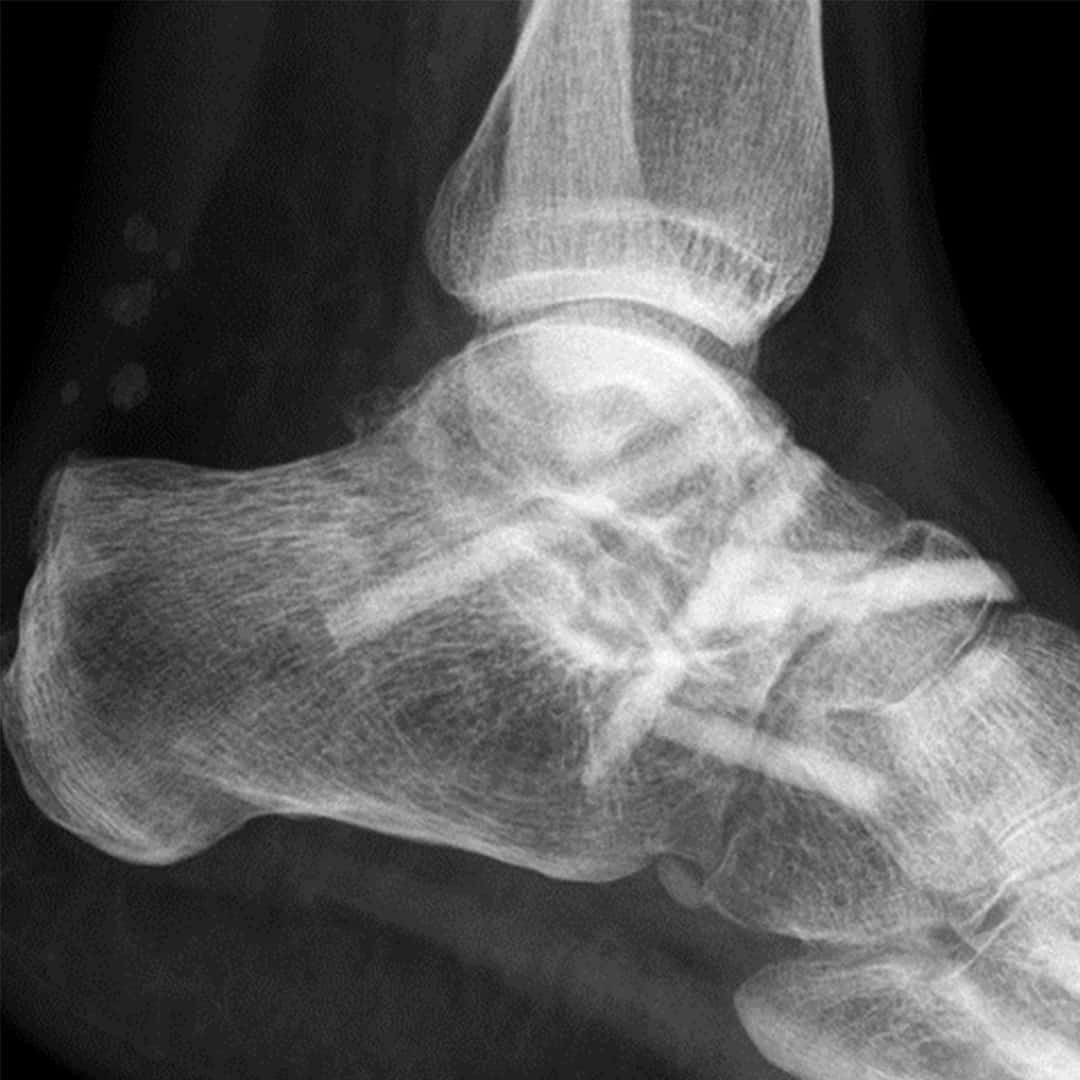

Triple-Arthrodese 8 Wochen postoperativ mit Shark Screw®